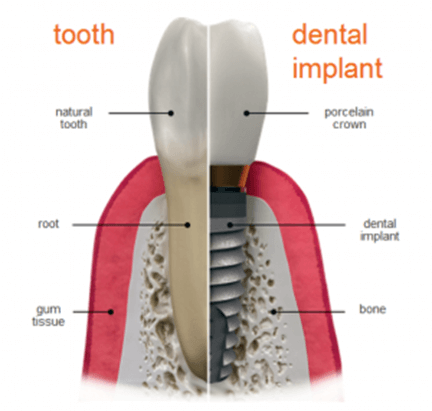

A type of dental treatment which is intended to replace a significantly damaged natural tooth with a replacement tooth is what one means by implants. It’s basically an invasive process which replaces the root of the teeth with screw like titanium posts, and then places the replacement teeth which looks as well as functions completely natural. If you are looking for an alternative to denture, partial denture or dental bridge have a talk with our Ottawa Denture Implant Centre for this surgery which allows chewing for all types of food.

- A metal post is placed which functions as an artificial tooth root.

- Placement of the artificial tooth.